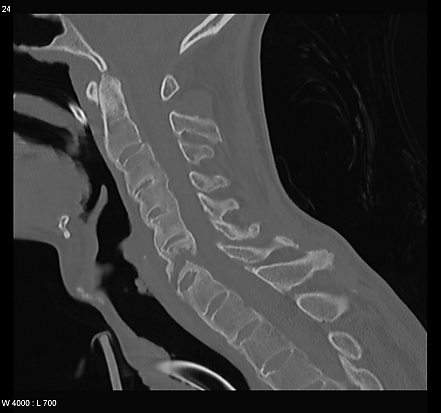

Перелом позвоночника

Перелом позвоночника — патологическое состояние, возникающее в ходе нарушения анатомической целостности костей позвоночника. Происходит под воздействием силы, вызывающей резкие и чрезмерные сгибания позвоночника или при непосредственном воздействии силы (травма). Все переломы позвоночника можно разделить на ряд групп в зависимости от положения перелома и его характера[2]:

- Перелом шейного отдела позвоночника

В этой части рассмотрены повреждения, которые чаще всего отмечаются на уровне с C3 до C7 позвонков.